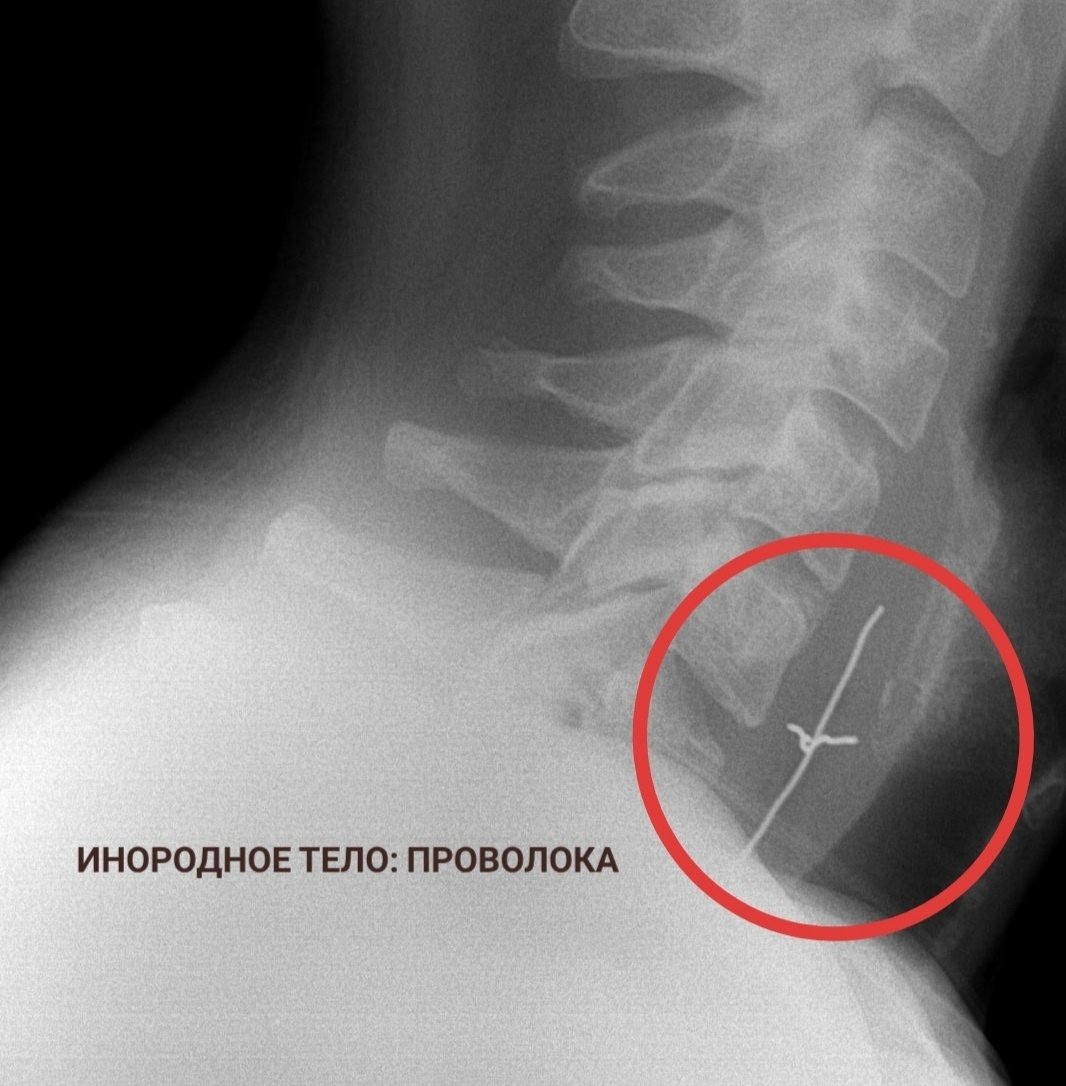

Stavropol.Media, 3 февраля. Проволока, бутылка и батарейки — эти и многие другие предметы извлекли из ставропольцев в 2025 году. Подборкой необычных находок внутри пациентов поделилась городская клиническая больница Пятигорска в своих соцсетях.

Специалисты удаляли монеты, металлические пластины с шурупами, а ещё фруктовые косточки и коронки.

"Случаи курьёзные, но проблема на самом деле серьёзная — ежегодно в ГКБ Пятигорска поступают десятки пациентов с инородными телами. Среди них немало детей. И им, как правило, требуется экстренная медицинская помощь", — напомнили в больнице.